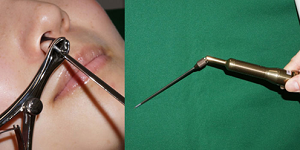

外来処置(レーザー治療)

| 鼻粘膜焼灼術 | アレルギー反応を鈍くさせるため、レーザーを使って鼻の粘膜の表面を焼灼します。痛みのない手術で、所要時間は麻酔に30分、手術は約5分で日帰り手術が可能です。個人差はありますが、有効率は70%で、2~3回の手術が必要です。 |

- アレルギー性鼻炎に対するレーザー治療

鼻の中に麻酔液を染み込ませたガーゼを30分間入れた後に3~4分間照射します。 痛みはありません。年中児から治療が可能です。内服薬の服用を約半分に減らせ、効果が数年持続します。 鼻中隔湾曲症では効果は限定的です。

鼻の中に麻酔液を染み込ませたガーゼを30分間入れた後に3~4分間照射します。 痛みはありません。年中児から治療が可能です。内服薬の服用を約半分に減らせ、効果が数年持続します。 鼻中隔湾曲症では効果は限定的です。- レーザー治療前後の鼻腔内所見